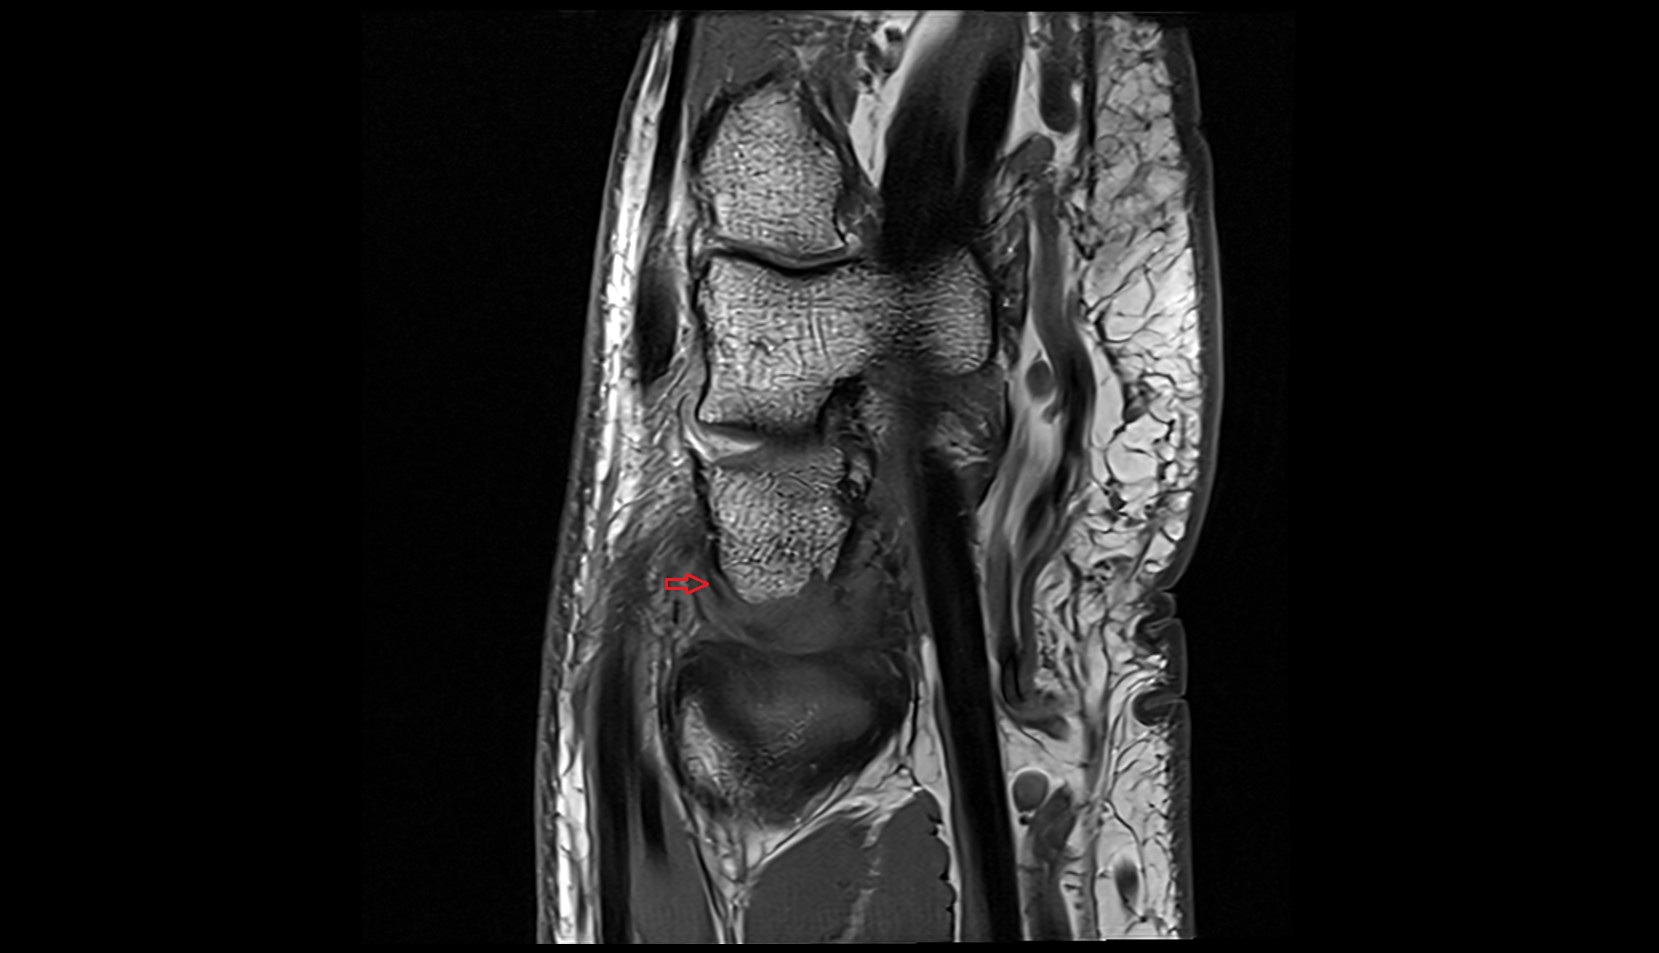

- Knee Joint